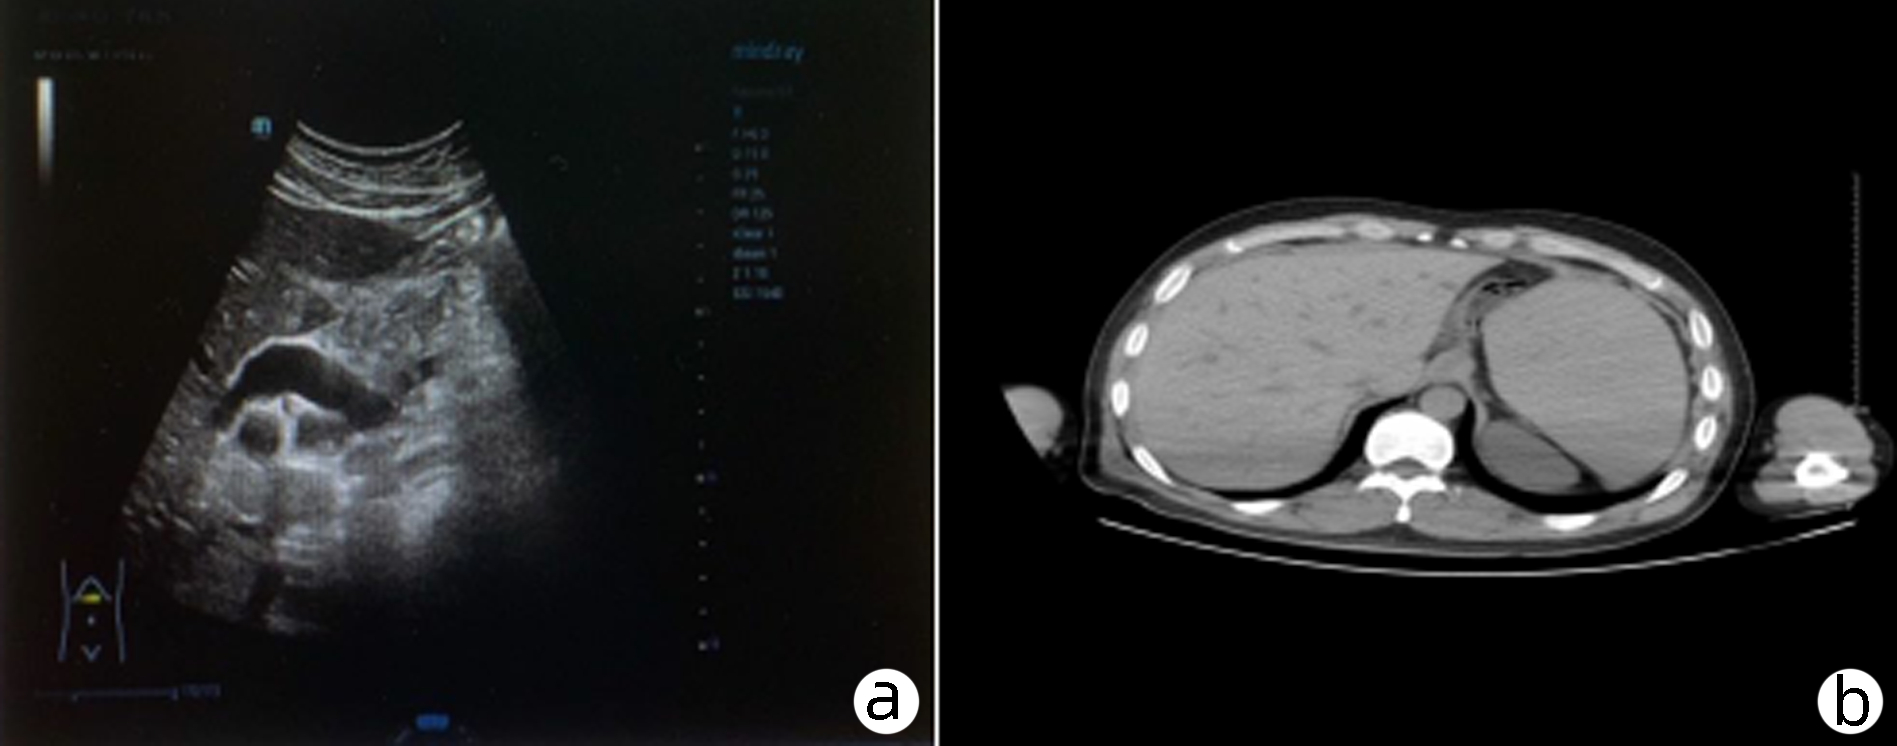

Sepsis with spontaneous splenic rupture and hemorrhage: A case report

Zhou LIU, Wenfang XIA, Liying ZHAN, Xiaoyu FANG, Liang ZHANG, Na ZHAN, Rong YU, Li HANG, Lei ZHU

2023, 39(8): 1926-1931. DOI: 10.3969/j.issn.1001-5256.2023.08.024

Abstract(1289) HTML (293) PDF (4249KB)(98)

Abstract:

Severe infections due to sepsis often result in multi-organ insufficiency, such as cardiac insufficiency, renal insufficiency, hypohepatia, septic encephalopathy, coagulation dysfunction etc. Severe infections not only cause inflammatory storm, but also induce spleen abscess, and even combined with spontaneous splenic rupture hemorrhage. Spontaneous splenic rupture has an insidious onset, usually without a history of trauma, and is easily missed diagnosis. In this case, the patient with sepsis had sudden onset of abdominal pain and progressive decrease in hematocrit, thus the abdominal CT was immediately performed. The perisplenic mixed high-density shadow indicated splenic hemorrhage. After consultation with the department of hepatobiliary surgery, emergency dissection was performed. Splenic hematoma and laceration were found during the operation, thus total splenectomy was conducted. Pathological indicated chronic inflammatory cell infiltration of spleen, spleen abscess with bleeding. After operation, the patient's hematocrit was stable, abdominal pain improved significantly, and he was discharged from hospital after systematic therapy.